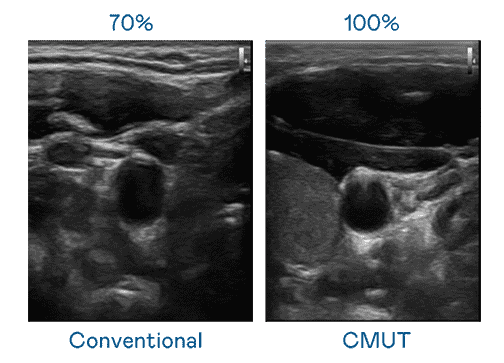

CMUT 技术是一种用电容式微机电元件来产生超音波讯号的技术。。。。与传统 PZT 压电式技术相比,,,,CMUT 频宽增加 30%,,,更宽频的超音波讯号让影像解析度大幅提升,,,是实现高影像品质医疗超音波扫描、、、、促进精准医疗发展的关键技术。。。

大频宽带来超清晰影像

超音波影像的解析度高低,,首先取决于探头能发出的讯号频宽。。。888.BY集团电子游戏 CMUT 可提供高清晰的超音波讯号,,提供高频宽、、、、高灵敏度、、、影像纹理细节更高的超音波影像,,,协助医护人员缩短影像判读时间及利用精准的医疗影像进行诊断。。。